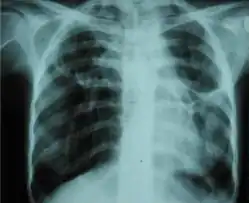

O diagnóstico de fibrotórax é normalmente feito por meio de um histórico médico adequado, combinado com o uso de técnicas de imagem apropriadas, como radiografia simples de tórax ou tomografia computadorizada.[3] Essas técnicas de imagem podem detectar o fibrotórax e o espessamento pleural que envolve os pulmões.[7] A presença de uma casca espessada com ou sem calcificação é uma característica comum do fibrotórax quando a imagem é obtida.[3] As tomografias computadorizadas podem diferenciar mais prontamente se o espessamento pleural se deve à deposição de gordura extra ou ao verdadeiro espessamento pleural do que os raios-x.[3]

Se o fibrotórax for grave, o espessamento pode restringir o pulmão do lado afetado, causando perda de volume pulmonar.[7] Além disso, o mediastino pode ser fisicamente deslocado para o lado afetado.[3] Uma redução no tamanho de um lado do tórax (hemitórax) em uma radiografia ou tomografia computadorizada do tórax sugere cicatrização crônica.[6] Sinais da doença subjacente que causa o fibrotórax também são ocasionalmente observados na radiografia.[6] A tomografia computadorizada pode mostrar características semelhantes às observadas em uma radiografia simples.[7] O teste de função pulmonar demonstra normalmente achados consistentes com doença pulmonar restritiva.[6]